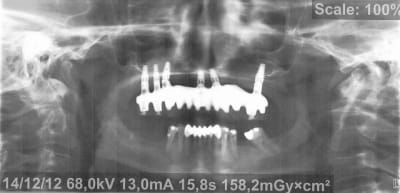

Voici donc les panos pour vos petits yeux ébahis

Profitez bien : elles sont ds l ordre chronologique...

(On est loin de tout comprendre sur les panos un peu floue, si ce n'est qu'à la fin totu est perdu)

Je vous donne une petite info : le comblement au BioOss a échoué largement...et on lui propose des greffes crâniennes à présent

Qu en pensez vous ??????????

- On y voit un manque flagrant de densité du greffon

- On y voit une perte d'un implant sans changement de plan de traitement, on se retrouve avec un seul implant du coté où mastique le patient

- On y voit une armature qui baille sur le seul implant qui reste secteur 2, et donc manque de passivité

- On y voit ce qui devait arriver,

Mais je vois aucun rapport entre l’échec et la nature du matériau mis en place dans le sinus....

Il est prévu de déposer également l'implant en position 26, ou bien a-t-il été laissé pour une raison précise ?

Il a été "abandonné" là mais il est douloureux et va être déposé sous peu